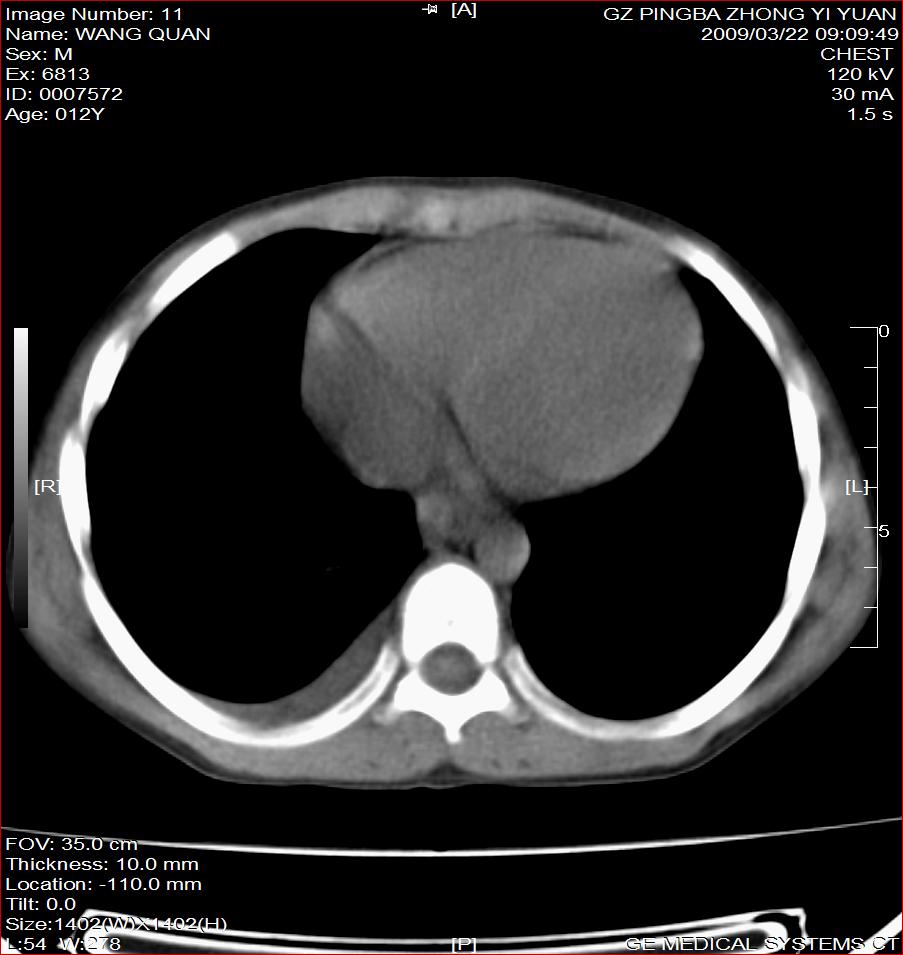

以下是引用随光逐影在2009-3-23 8:12:00的发言:[br]1)右肺门及纵隔淋巴结结核。2)两肺急性血行播散型肺结核可能。3)右侧支气管内膜结核?建议必要时行纤支镜检查。4)右侧少量胸腔积液。